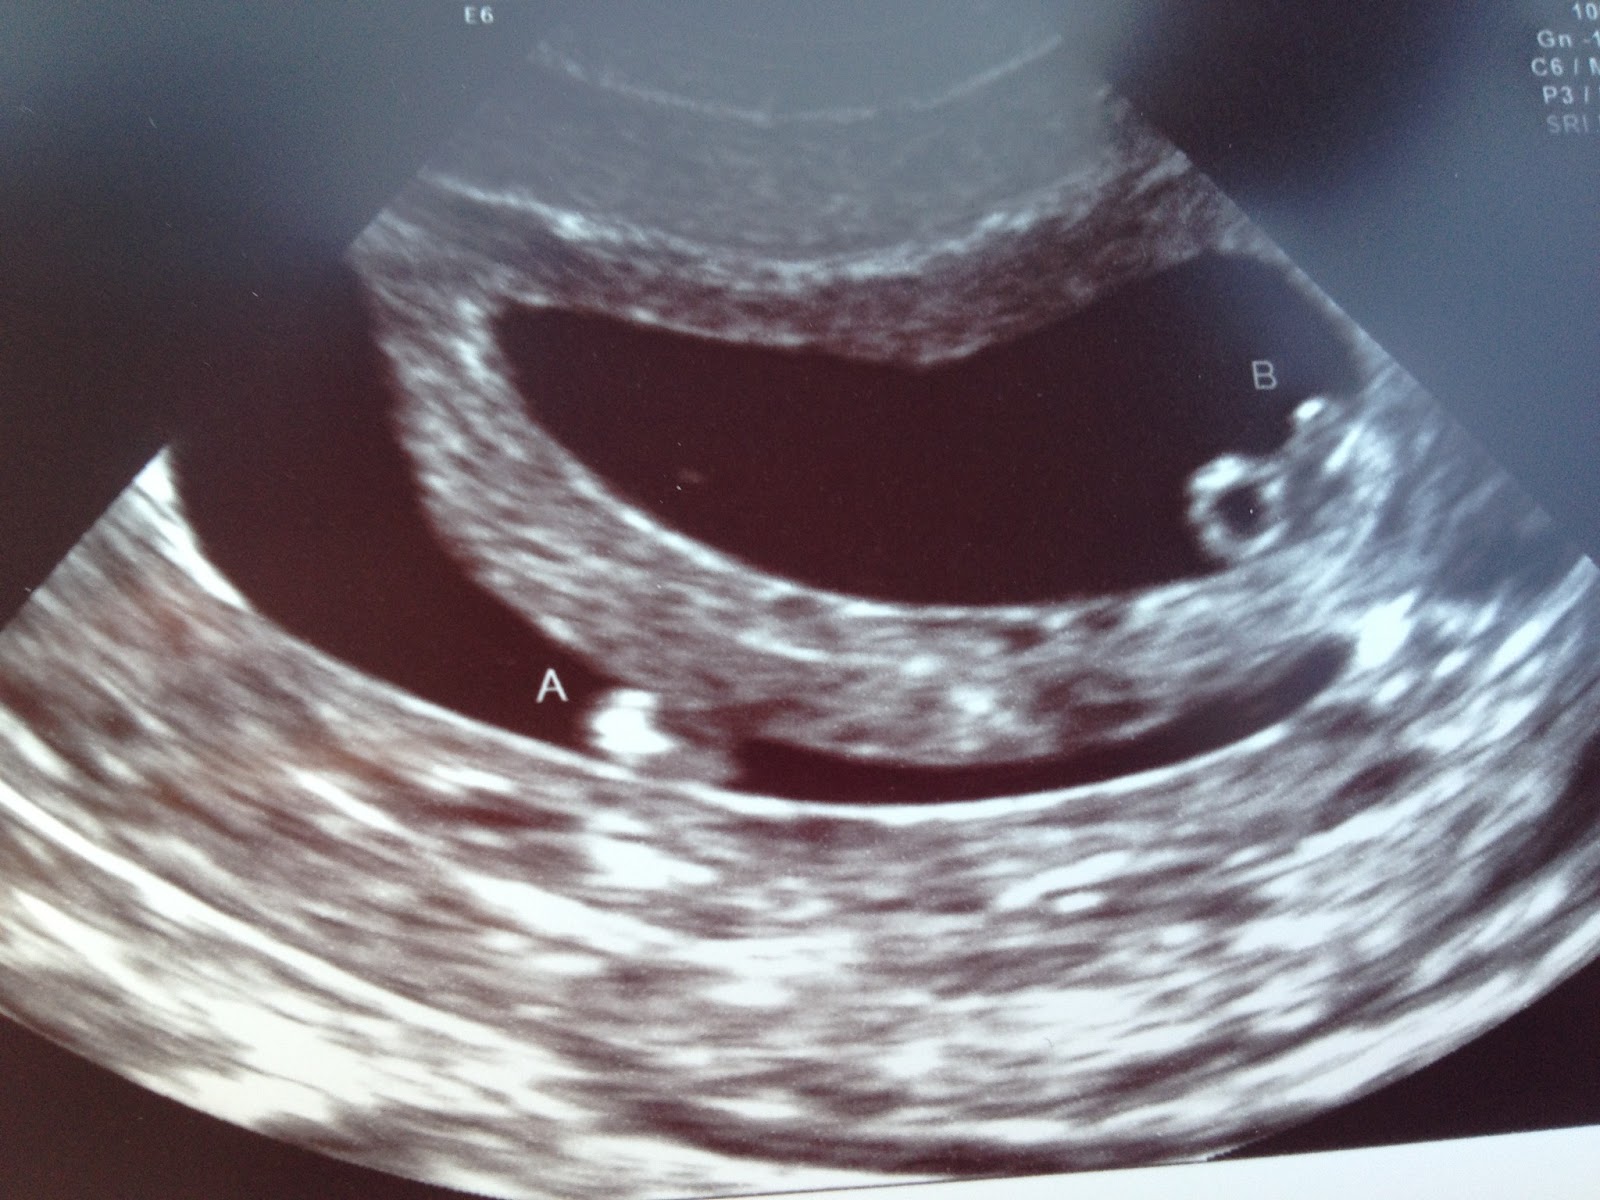

Twins 6 Weeks Pregnant Ultrasound. Twins Ultrasound 6 Weeks Complications like anemia and delayed fetal growth. A 3D ultrasound at 6 weeks is less common than the standard 2D ultrasound

6 Week Ultrasound Fraternal Twins. When you're 6+0 weeks pregnant, your baby's hearts should be beating - and the sonographer should be able to detect them at. At an ultrasound scan at 6 full weeks, a sonographer will most likely be able to spot any type of twin pregnancy